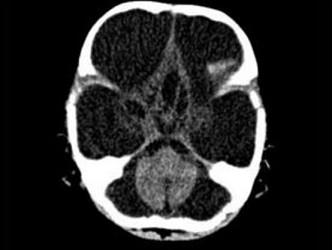

问题 3个月男婴,头颅迅速增大,发育停滞,CT表现如图,可能的诊断为 ( )

选项 A、先天性脑积水 B、重度脑积水 C、慢性双侧性巨大硬膜下血肿 D、水瘤 E、脑严重缺血

答案 A